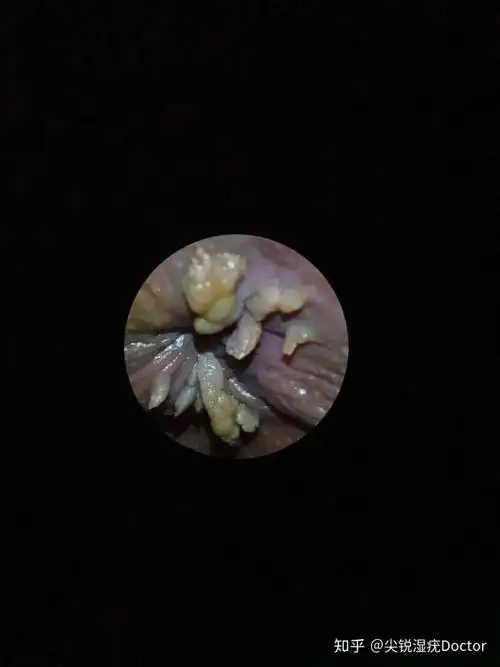

我也是头一次见这么大的菜花疣,一般都在口腔或者生殖器周围.# - 抖音

低危型hpv感染1,皮肤症状①寻常疣:米粒大小的丘疹,表面角化明显,粗糙